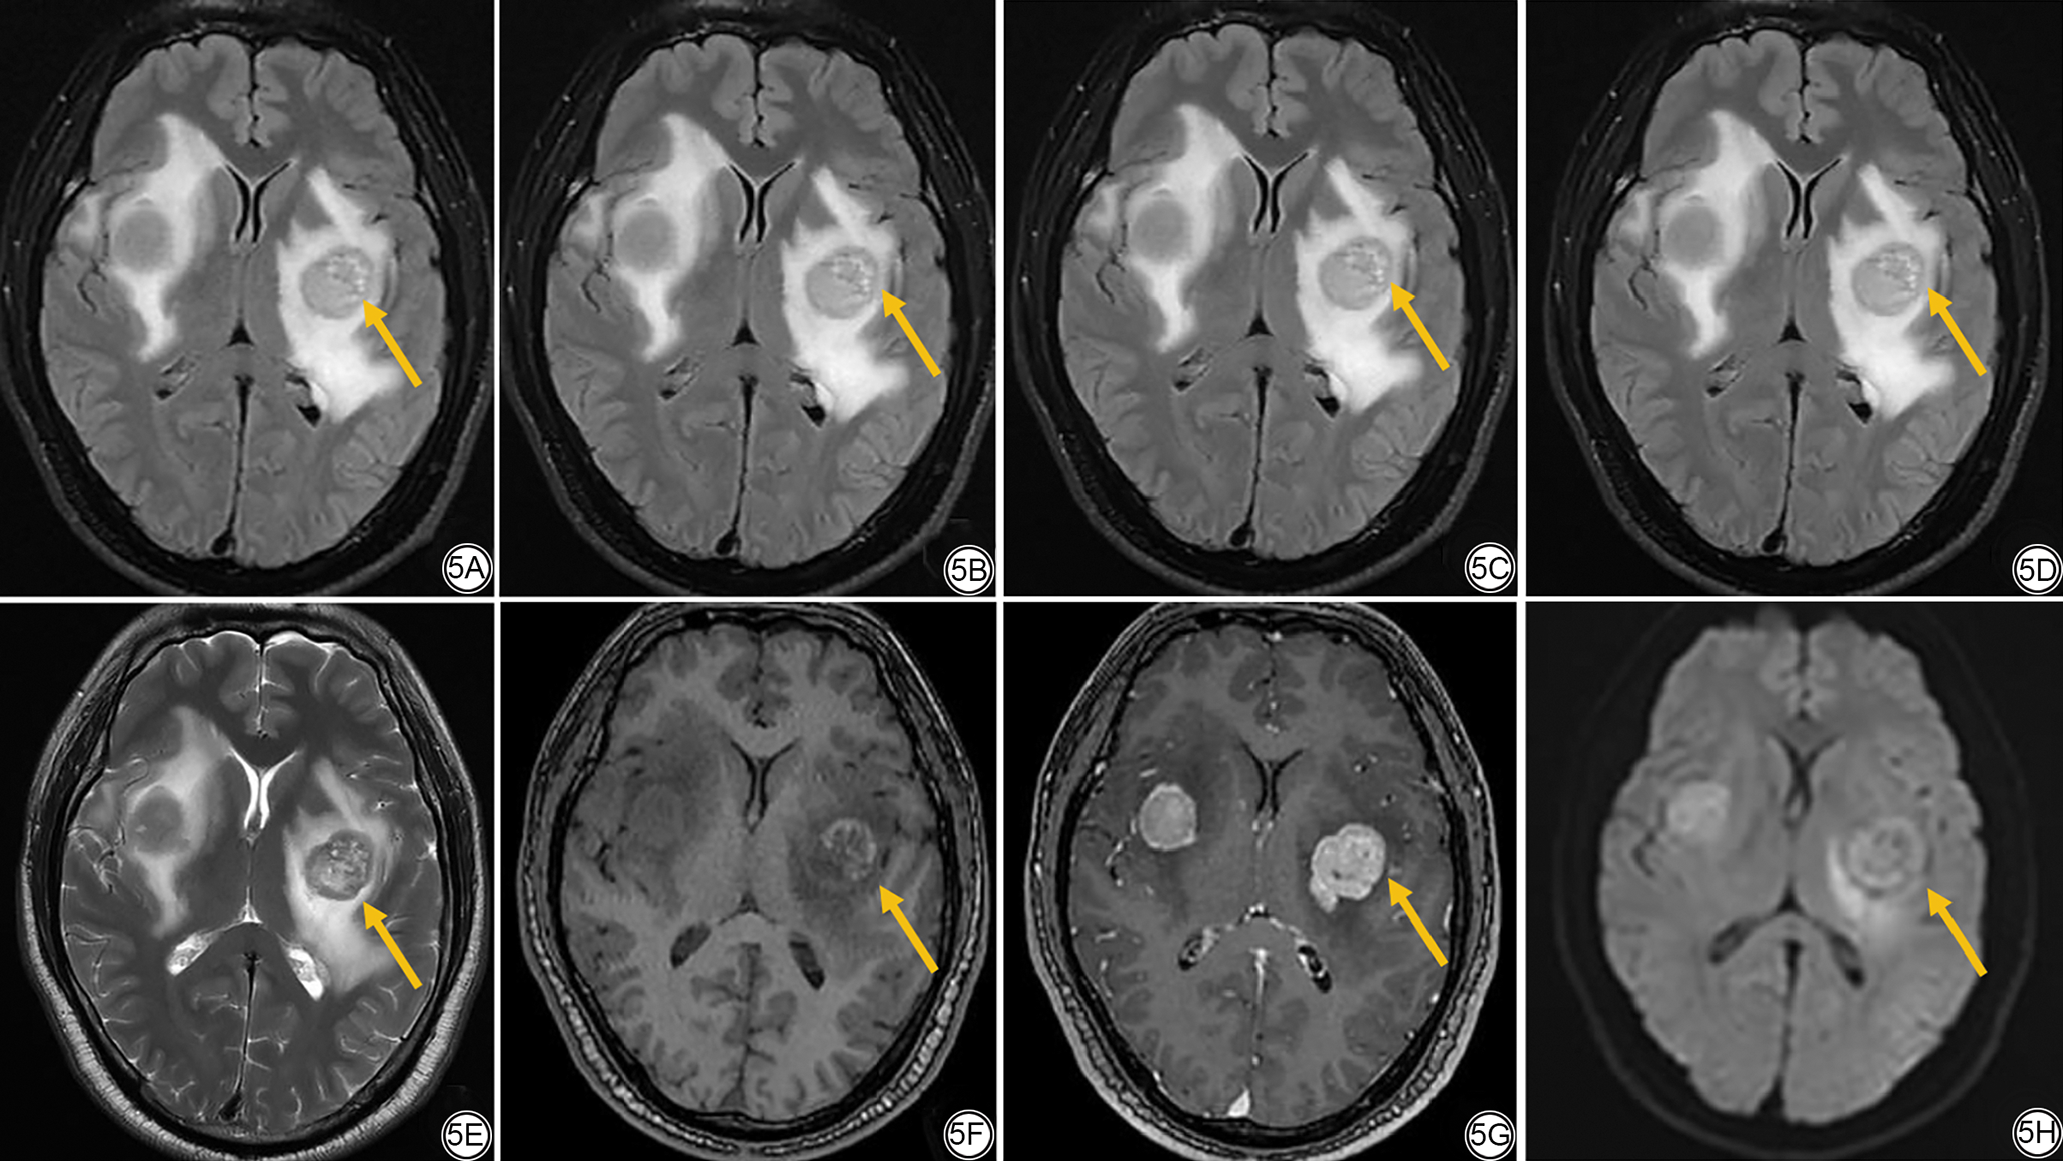

(1)定量评价。为减少偏差,定量评价采用以下标准流程:利用联影后处理工作站在双侧半卵圆中心、双侧尾状核、胼胝体压部、脑桥及双侧小脑最大正常层面放置大小合适的圆形ROI(半卵圆中心、脑桥和小脑ROI约50 mm2,尾状核ROI约20 mm2,胼胝体压部ROI约30 mm2),避开血管、脑脊液、伪影及病变,测量其SI以及SD,取双侧对称结构的测量值取平均值(图1)。将双侧半卵圆中心SI及SD的平均值分别作为背景信号(background signal intensity, SIb)和背景标准差(SDb),据此计算各区域的SNR和对比噪声比(contrast-to-noise ratio, CNR),见公式(4)[23]

图1  ROI勾画示意图。1A:双侧半卵圆中心;1B:双侧尾状核;1C:胼胝体压部;1D:脑桥;1E:双侧小脑。ROI:感兴趣区。

Fig. 1  ROI schematic diagram. 1A: Bilateral centrum semiovale; 1B: Bilateral caudate nuclei; 1C: Corpus callosum compression; 1D: Pons; 1E: Bilateral cerebellum. ROI: region of interest.